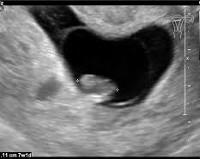

• УЗИ полости матки. Размер матки составляет 2 недели или дольше после периода беременности. В первом триместре можно определить анембрионию - пустое плодное яйцо. В других случаях сердцебиение плода отсутствует, а через 12 недель нет признаков движения.